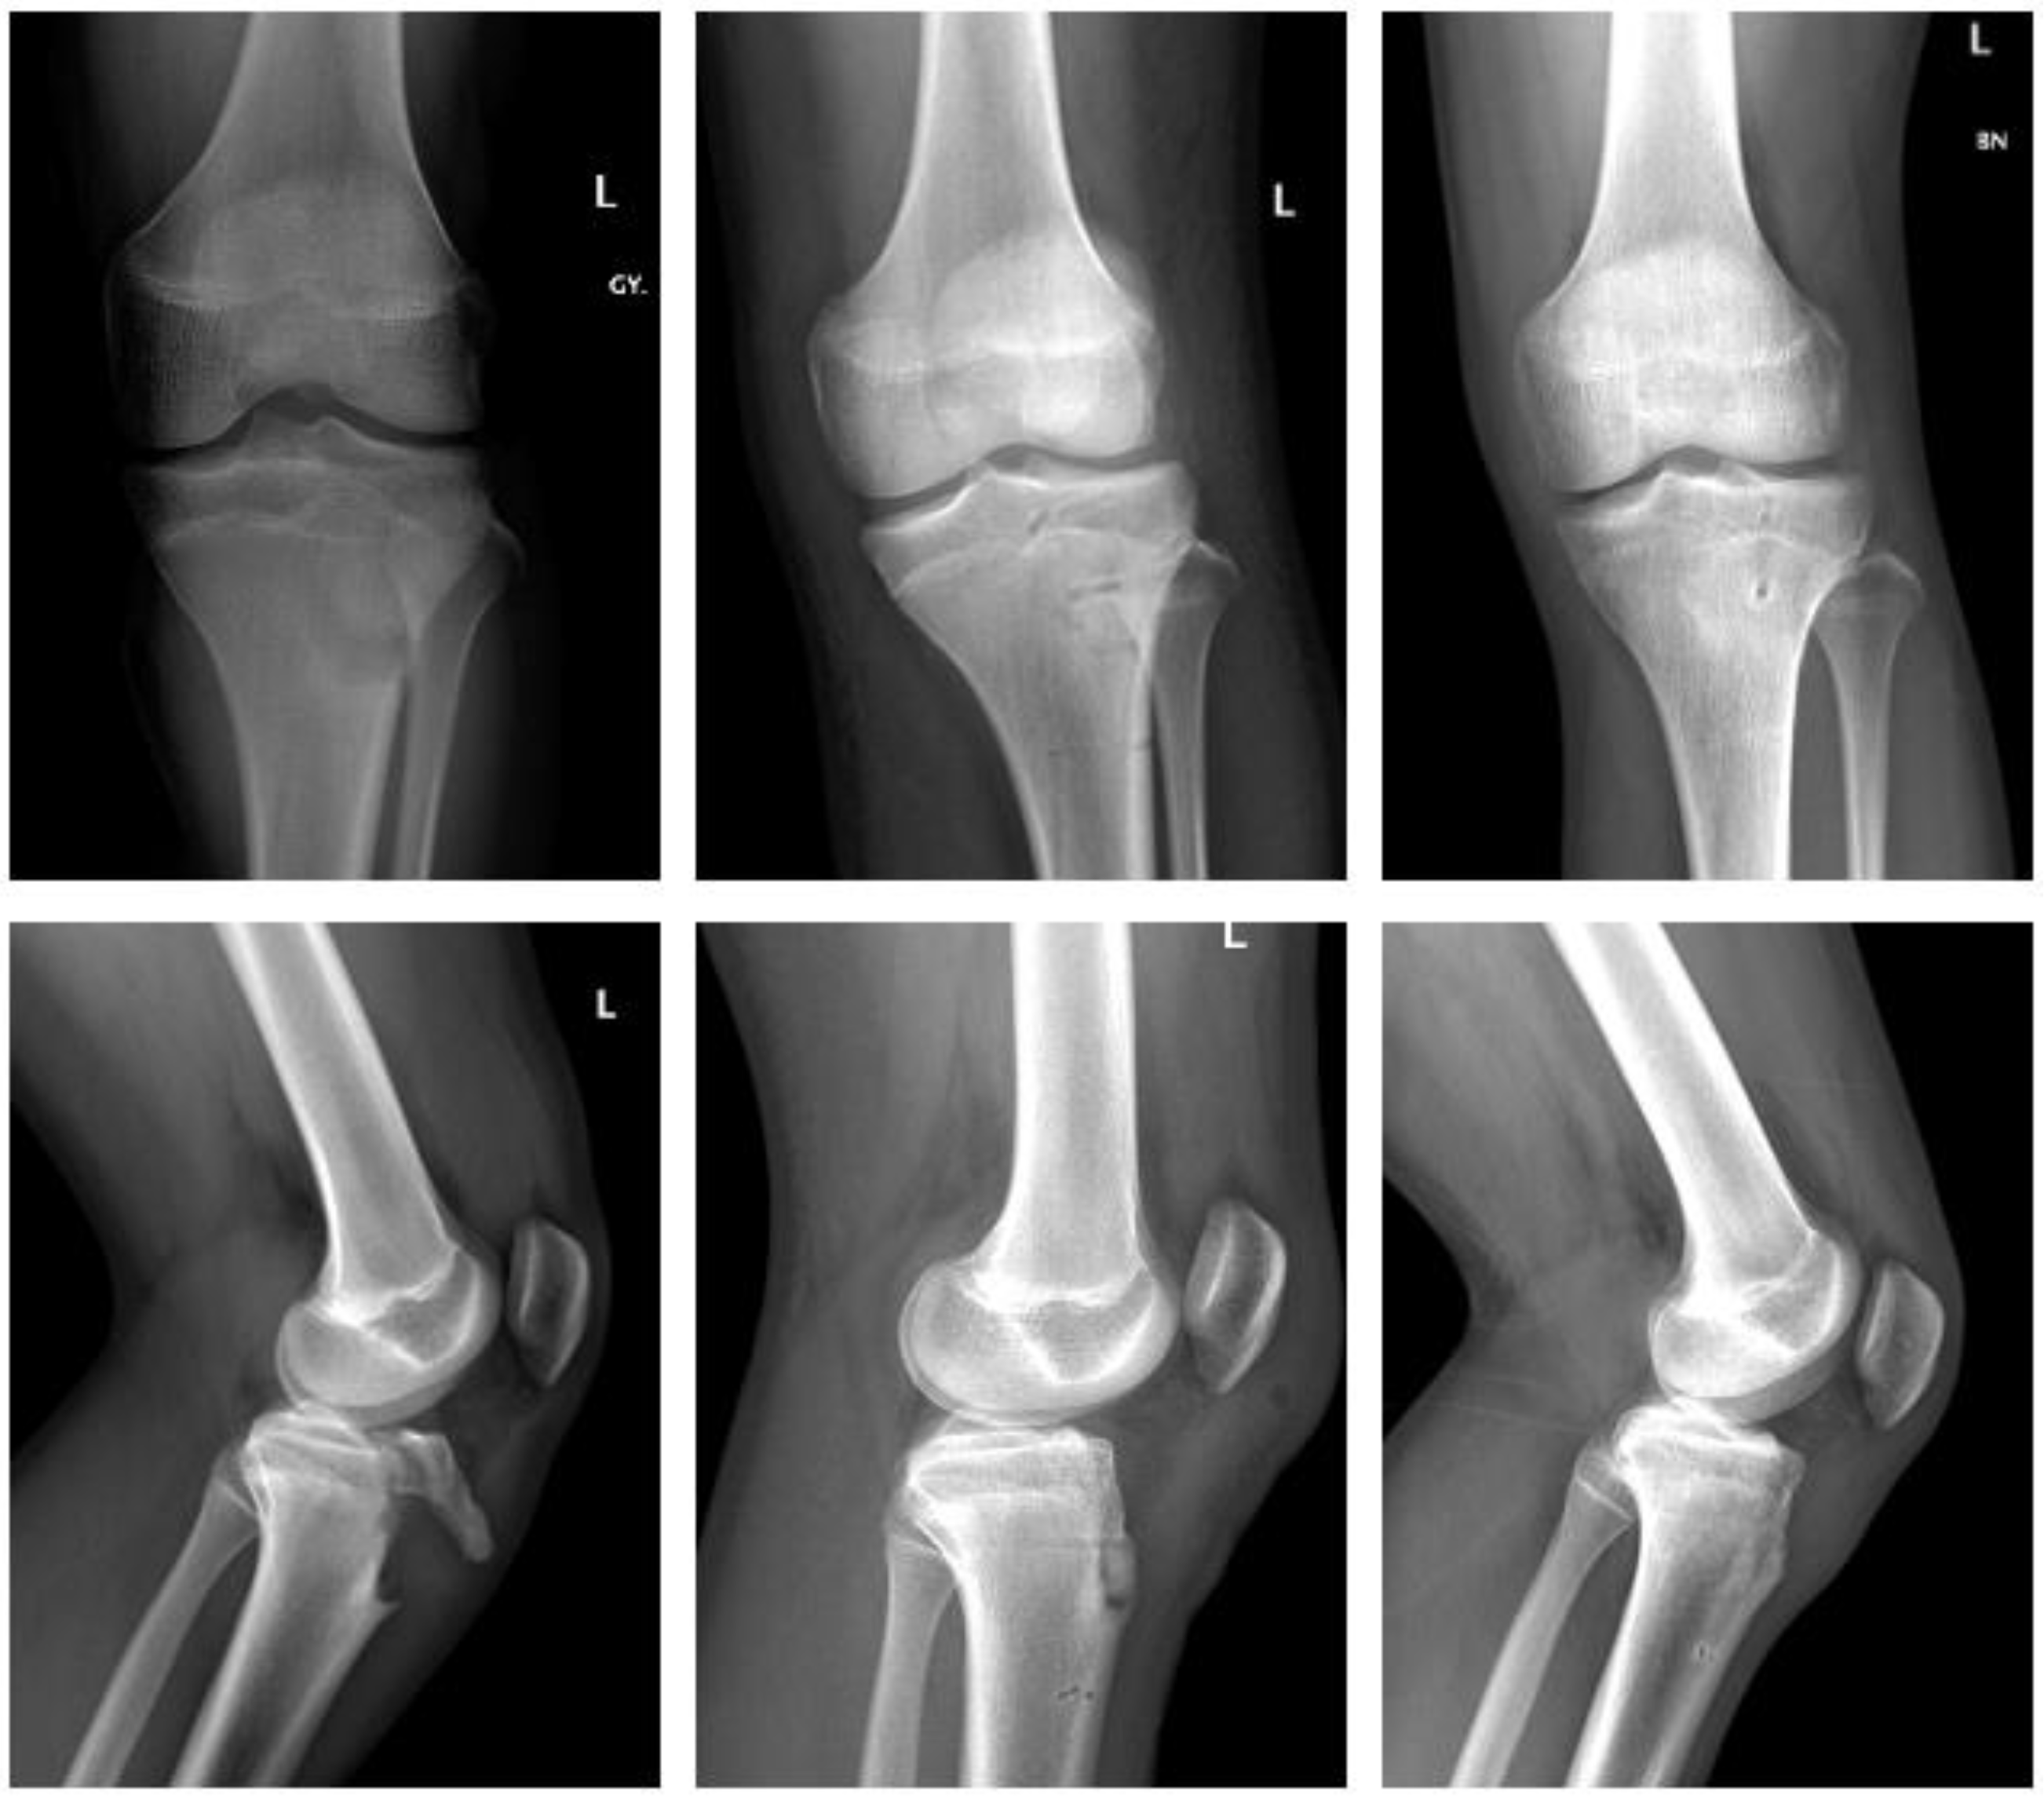

2.4.1. Fracture of the Tibial Tuberosity